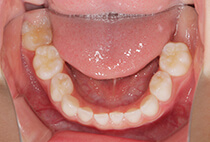

20代女性の患者さま。

八重歯の見た目が気になってご来院されましたが、実は顎の痛みや開口障害など、顎関節症の症状もありました。

そのため、かみ合わせと顎関節症の治療を同時に行ったにもかかわらず、2年間で治療が終了。

かみ合わせが整い咬筋の過緊張も改善しました。咬筋の肥大も治ってフェイスラインがすっきりしました。

最終的には美しい歯並びと、安定した痛みのないかみ合わせが実現しました。

八重歯が気になる

叢生、顎関節症、開口障害

20代女性

矯正治療2年

24回

唇側矯正

矯正:1,161,600円+毎月調整量:6,050円

しっかり前歯を下げるために、インプラントアンカーを使用してコントロールしました。

かみ合わせが整うと咬筋の過緊張が改善。

過緊張による筋肉肥大も改善しフェイスラインもすっきりしました。

治療前

治療後